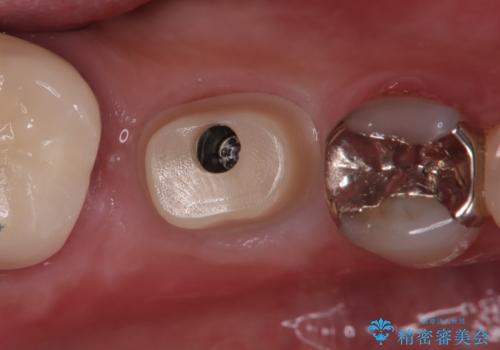

被せ物はオールセラミッククラウンを被せています。